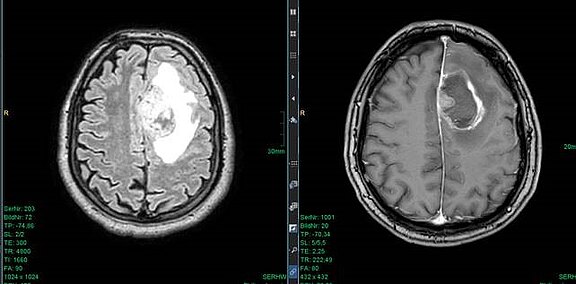

Neben der Entfernung des Hirntumors ist die Erhaltung aller Gehirnfunktionen Ziel der Operation. Dies schaffen wir durch modernste elektrophysiologische und präoperative Mappingmethoden. Das erfordert viel Umsicht in der Diagnose, weswegen wir vorweg verschiedene Untersuchungen durchführen. Beispielsweise helfen bildgebende Verfahren, Lage und Größe des Tumors genauestens zu bestimmen. Auch die aktuelle Gesundheit und das Alter der Patientinnen und Patienten werden beachtet.